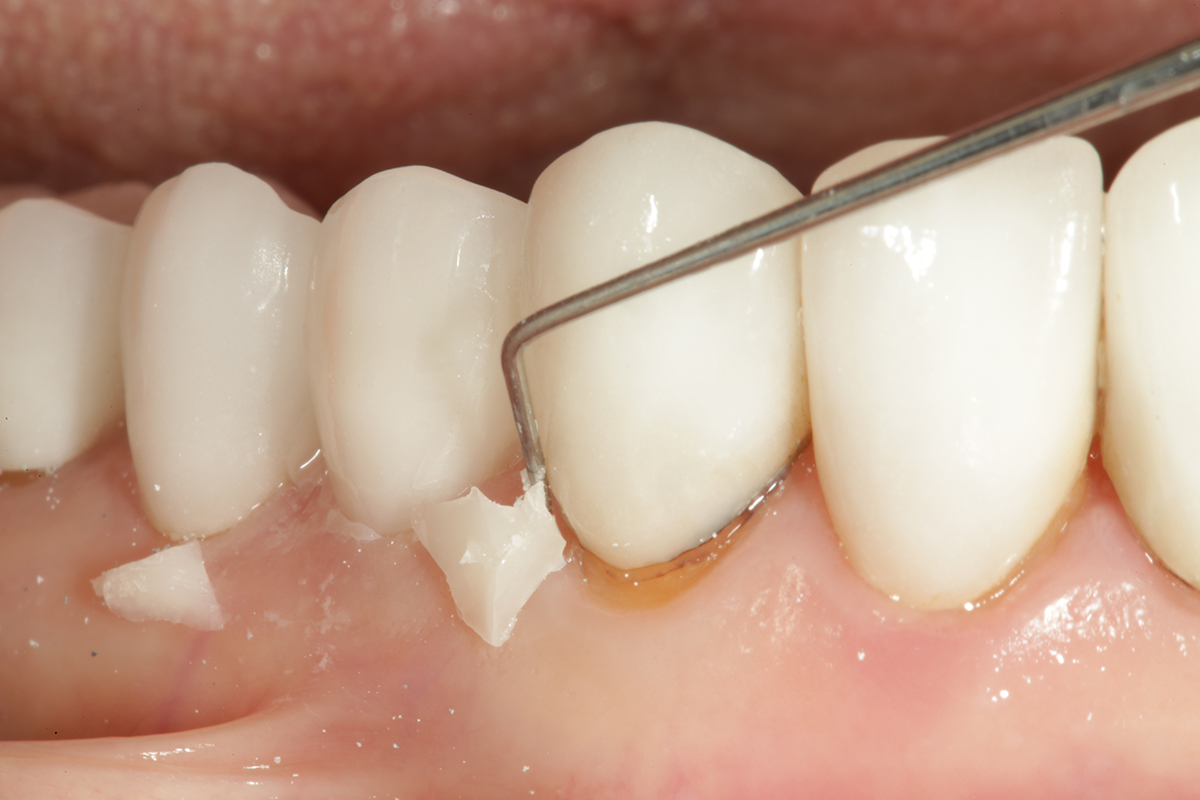

Fig 18. After the gel set is reached (approximately 90 to 120 seconds), the excess cement can be carefully removed around the margin with an explorer.

Figure 18

Fig 19. An interproximal strip (ContacEZ) can be used to remove any excess cement that may be lodged in the contact areas prior to flossing.

Figure 19